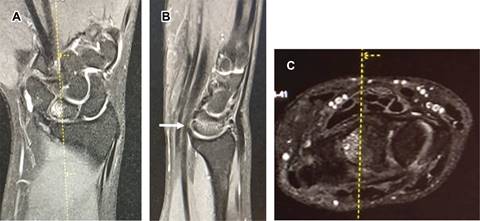

Femenino de 28 años, con dolor de un año en cara dorsal de muñeca, las radiografías simples fueron normales (Figura 1). La resonancia magnética (RM) (Figura 2) mostró incremento de señal en la porción medial del semilunar derecho, correspondiendo a necrosis avascular del semilunar (enfermedad de Kienböck), entidad descrita en 1913, caracterizada por necrosis del hueso semilunar. Generalmente afecta a varones entre los 20 y 40 años, originada por interrupción de la vascularización del hueso semilunar, que inicialmente sufre isquemia y posteriormente necrosis, ocasionando artrosis de muñeca; tiene origen multifactorial, como: factores genéticos, anatómicos, vasculares, traumáticos y ocupacionales. Los pacientes generalmente consultan por dolor de larga evolución, generalmente centrado en el dorso de la muñeca que empeora con la actividad física, puede haber inflamación difusa y dificultad para soportar carga. El diagnóstico clínico debe confirmarse mediante radiografías (que en fases iniciales pueden ser normales) y RM. El tratamiento depende de la etapa de la enfermedad, diferenciando entre estadios aún reversibles o no; en los primeros, las técnicas incluyen injertos vascularizados y las osteotomías de acortamiento para quitar presión al hueso semilunar. En etapas irreversibles, las distintas posibilidades para mejorar la función incluyen las denervaciones, la resección de primera fila del carpo y artrodesis parciales, como último recurso para el control del dolor se reserva la artrodesis total de muñeca.

Figura 1: Radiografías anteroposterior y lateral del carpo derecho. Se observa forma y posición normal del hueso semilunar, en femenino de 28 años con dolor en dorso de muñeca de un año de evolución, en quien se sospechó clínicamente enfermedad de Kienböck.